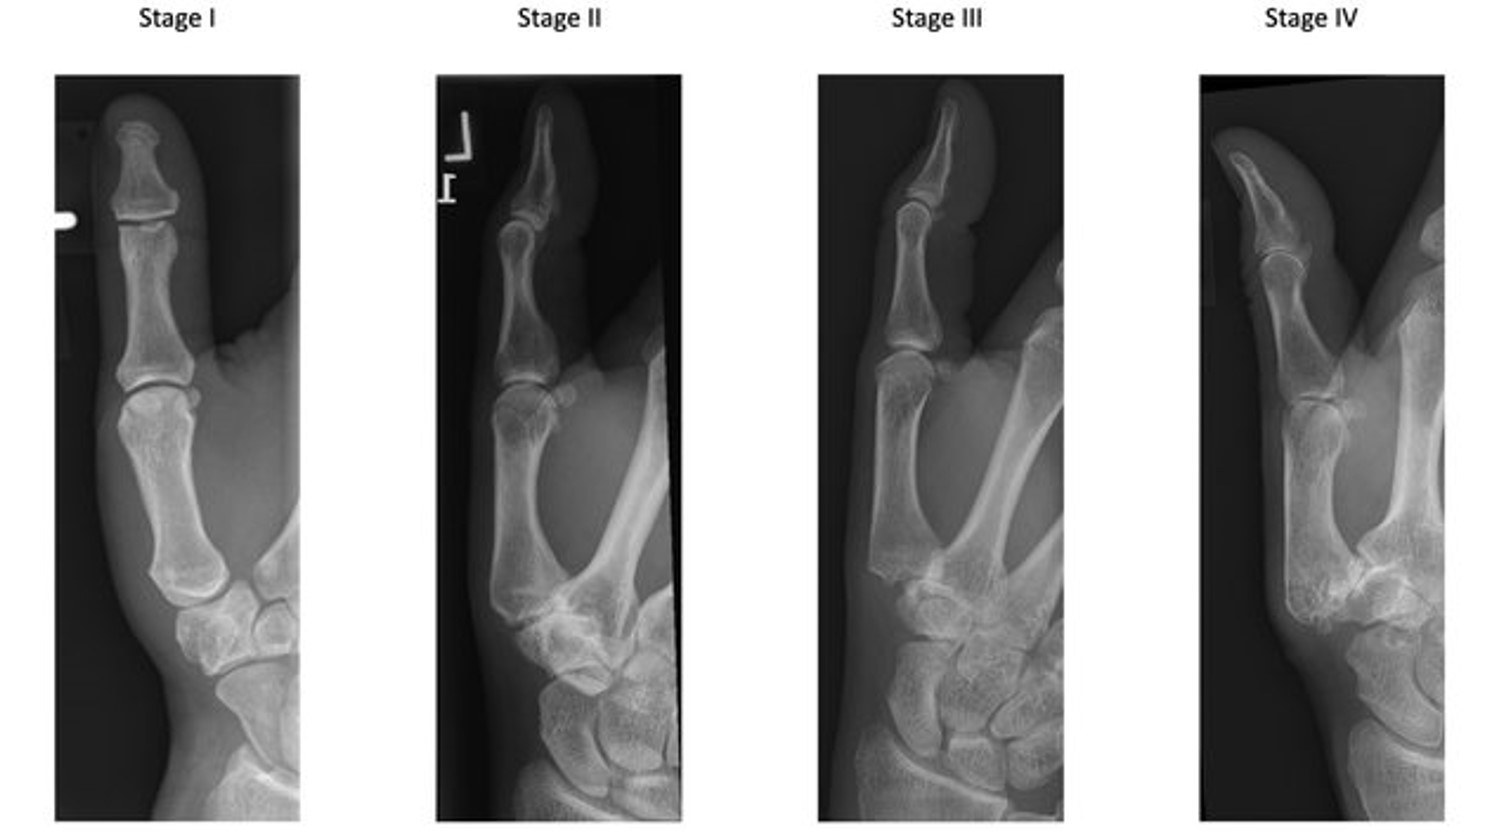

Radiografische classificatie van duimbasisarthrose